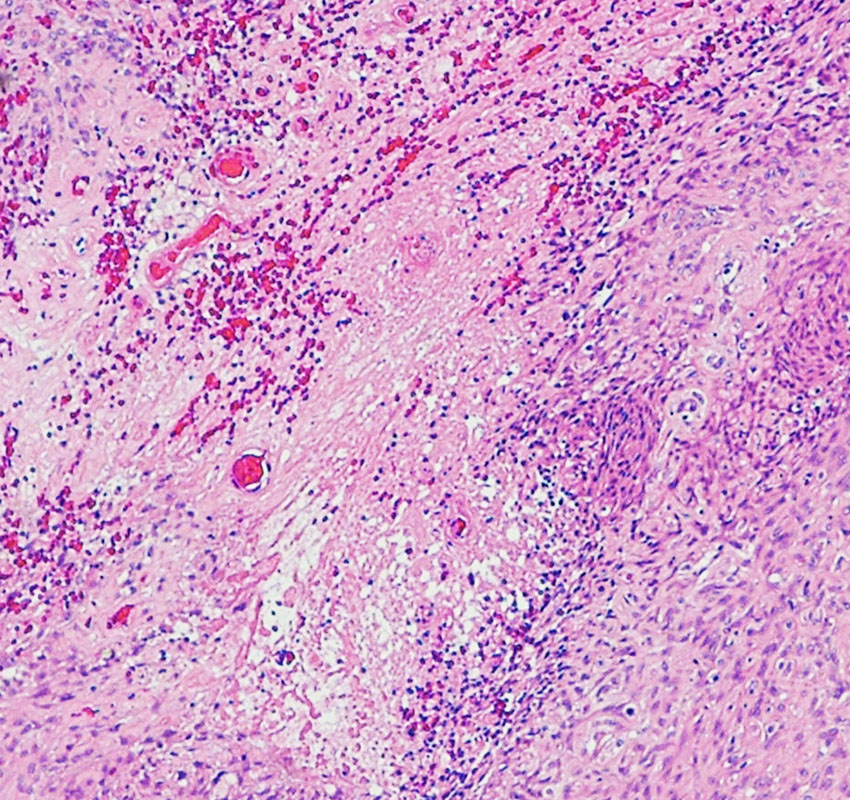

necrosis 壊死・atypical meningioma WHO grade 2 非定型髄膜腫

WHO grade 2 atypical meningioma (MIB-1 15%)に認められた壊死像です。この病理部分像からはgrade 2ですが,MIB-1も非常に高率です。さらに,多少なりとも核異型がみられるとgrade 3のanaplastic meningiomaになります。